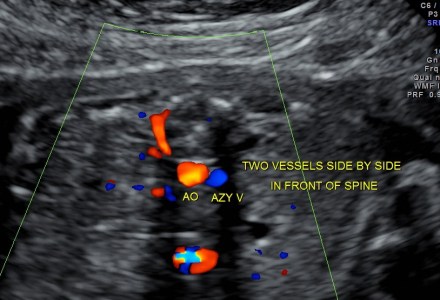

LEFT ATRIAL ISOMERISM , SITUS AMBIGUUS (or AMBIGUOUS), HETEROTAXY